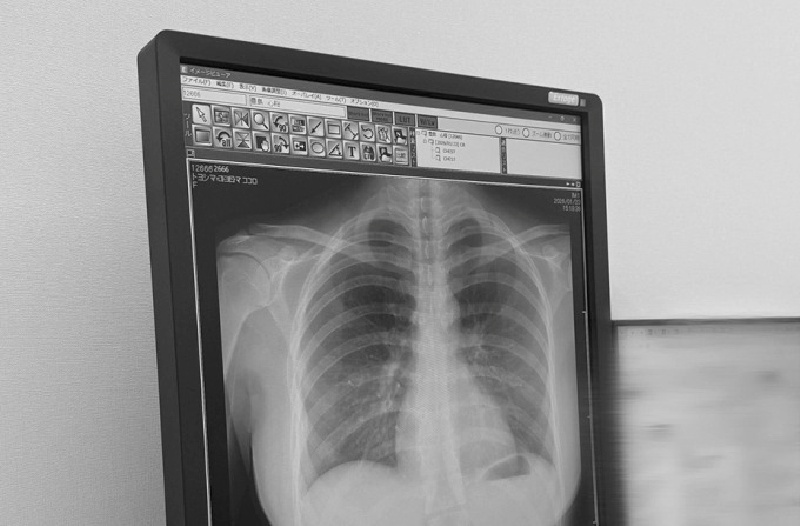

Sự việc bắt đầu vào ngày 23/1, khi nữ người mẫu 22 tuổi đăng tải ảnh phim X-quang lên nền tảng X, kèm dòng chú thích ngắn gọn: “Phổi của tôi rất sạch”. Theo Oricon News, Toyoshima chỉ đơn thuần muốn cập nhật tình trạng sức khỏe với người hâm mộ sau buổi kiểm tra định kỳ.

Tuy nhiên, bức ảnh đen trắng nhanh chóng lan truyền với tốc độ chóng mặt, đạt hơn 43 triệu lượt xem và 58.000 lượt thích tính đến ngày 25/1. Điểm thu hút sự chú ý không nằm ở kết quả y tế mà là cấu trúc xương và đường cong cơ thể hiện rõ trên phim chụp. Nhiều khán giả nhận xét hiếm thấy tấm phim X-quang nào vẫn lột tả được trọn vẹn vóc dáng người chụp, đặc biệt là khuôn ngực cup H nổi tiếng của nữ thần tượng, theo VnExpress.

Bức ảnh X-quang của nữ người mẫu Nhật "gây bão" mạng xã hội với 43 triệu view. Ảnh: VnExpress.